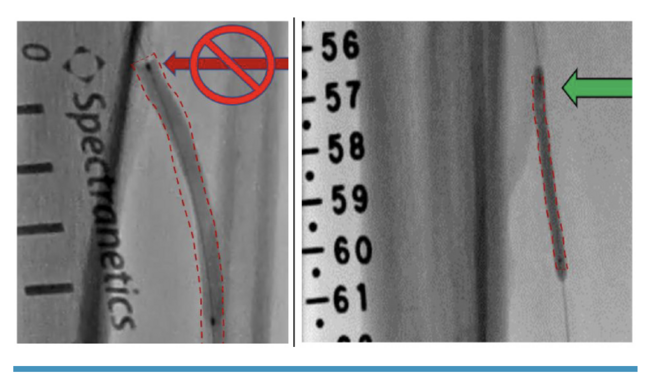

In order to achieve successful deployment of the MicroStent, device deployment should be slow and steady to avoid elongation and stacking, which can reduce the designed engineering properties of the MicroStent. For lesions requiring multiple MicroStents, a ~1 cm overlap is recommended. Deployment should always be distal to proximal (anatomically) such that the proximal stent (upstream) lays within the distal stent (downstream). After completion of MicroStent deployment, postdilation is strongly recommended. The labeled diameter of the balloon used should not exceed the diameter of the MicroStent. The operator should ensure that distal and proximal ends of the stent are adequately dilated. The balloon should extend just outside of the stent end to ensure full dilation (Figure 4).